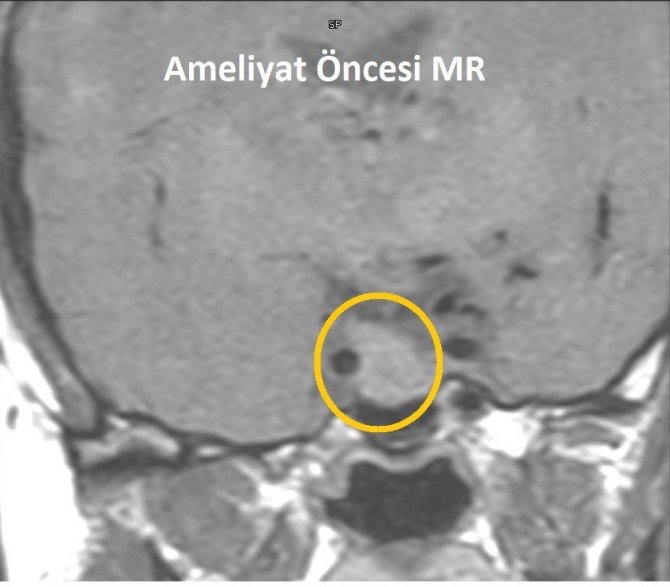

Mersin'de baş ağrıları ve adet düzensizlikleri nedeniyle hastaneye başvuran kadında iyi huylu hipofiz tümörü tespit edildi. 41 yaşındaki Hamde Alahmad, kafatası açılmadan burundan girilerek yapılan ve yaklaşık 3 saat süren operasyonla sağlığına kavuştu.

VM Medical Park Mersin Hastanesi'nde adet düzensizlikleri ve baş ağrıları nedeniyle yapılan tetkiklerde hipofiz bezi yerleşimli yaklaşık 2 santimetre boyutlu adenom (iyi huylu hipofiz tümörü) tespit edilen 41 yaşındaki Hamde Alahmad, başarılı bir ameliyat ile tedavi edildi. Kafatası kemiği açılmadan burundan endoskop ve nöronavigasyon gibi yüksek teknolojiler kullanılarak gerçekleştirilen ameliyatı, hastane dışından Kulak Burun Boğaz Uzmanı Prof. Dr. Hayrettin Cengiz Alpay, VM Medical Park Mersin Hastanesi Kulak Burun Boğaz Uzmanı Op. Dr. Aykut Bozan ve Beyin Cerrahisi Uzmanı Prof. Dr. Bora Gürer ile Op. Dr. Ramazan Fesli başarılı bir şekilde gerçekleştirdi.

Çok küçük boyutlarda tesadüfen tespit edilmiş, herhangi bir bulguya ve anormal hormon salgılanmasına neden olmayan adenomların tedavi edilmediğini vurgulayan Prof. Dr. Gürer, "Ancak çeşitli aralıklarla bu adenomların büyüyüp büyümediği takip edilmelidir. Nasıl bir tedavi uygulanacağı adenomun boyutuna, salgıladığı hormonun çeşidine ve neden olduğu bulgulara göre değişir. Bunlara ilaç tedavileri, radyasyon tedavisi ve cerrahi tedaviler uygulanabilmektedir. Bu hastamızda da 3 saat süren başarılı bir cerrahi işlem gerçekleştirilmiş olup, tekrar eski sağlığına kavuşturulmuştur. Tedavi sonrası belirli aralıklarla adenomun takip ve yeniden büyüyüp büyümediği kontrol edilecek" ifadelerini kullandı.